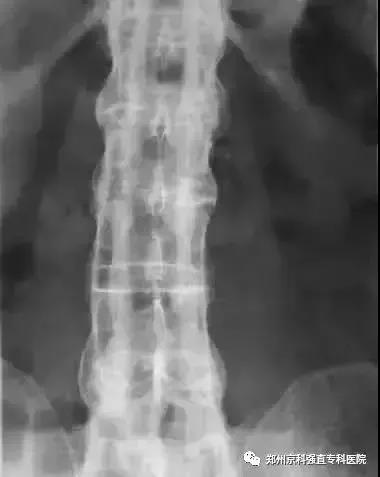

3、X线检查

98%~100%病例早期即有骶髂关节的X线改变,是本病诊断的重要依据。早期X线表现为骶髂关节炎,病变一般在骶髂关节的中下部开始,为两侧性。开始多侵犯髂骨侧,进而侵犯骶骨侧。可见斑点状或块状,髂骨侧明显。继而可侵犯整个关节,边缘呈锯齿状,软骨下有骨硬化,骨质增生,关节间隙变窄。最后关节间隙消失,发生骨性强直。